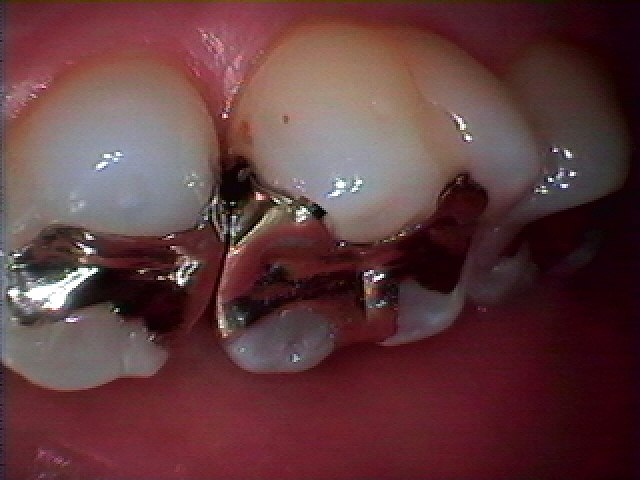

右上5,6番の銀歯をはずしていきます 銀歯の下には虫歯が存在していることがわかっています

銀歯をはずすとこのように大きく虫歯になっていました